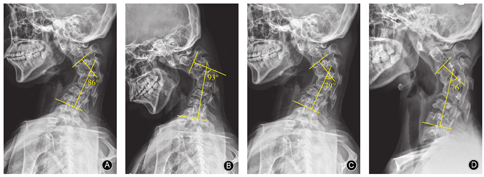

侧位X线片示颈椎后凸顶点为C3,4椎间隙,后凸Cobb角为86°,寰枢椎脱位伴失稳;过屈位X线片示后凸Cobb角为93°,过伸位X线片示后凸Cobb角为79°;颅骨牵引位X线片示后凸Cobb角为76°,柔韧度8.1%(图1)。未见骶髂关节硬化、融合等。

颈椎后凸畸形的主要影像学测量参数包括:①颈椎后凸Cobb角,即后凸上端椎上终板与下端椎下终板垂线所形成的夹角。②C2~C7角,即C2椎体下终板垂线与C7椎体下终板垂线所形成的夹角。③C0~C2角,即颅底连线与C2椎体下终板连线的夹角。④C7倾斜角,即C7椎体上终板延长线与水平线所形成的夹角。⑤C2~C7矢状位平衡(sagittal vertical axis,SVA),即通过C2椎体的几何中心(或齿突)垂线至经C7后上角垂线的水平距离[7,8]。⑥颈椎后凸指数(kyphosis index,KI):上端椎后上缘至下端椎后下缘连线的长度,并测量后凸内各椎体后下缘距此线的距离之和,两者比值即为后凸指数。颈椎后凸畸形严重的患者,为了维持水平视角,C0~C2角代偿性增大,非后凸节段过度前凸。Shen等[9]指出计算KI时,由于各椎体后上缘均在连线的后方,且结果显示KI与颈椎后凸Cobb角具有明显的相关性,因此,适合采用KI评估颈椎后凸畸形。